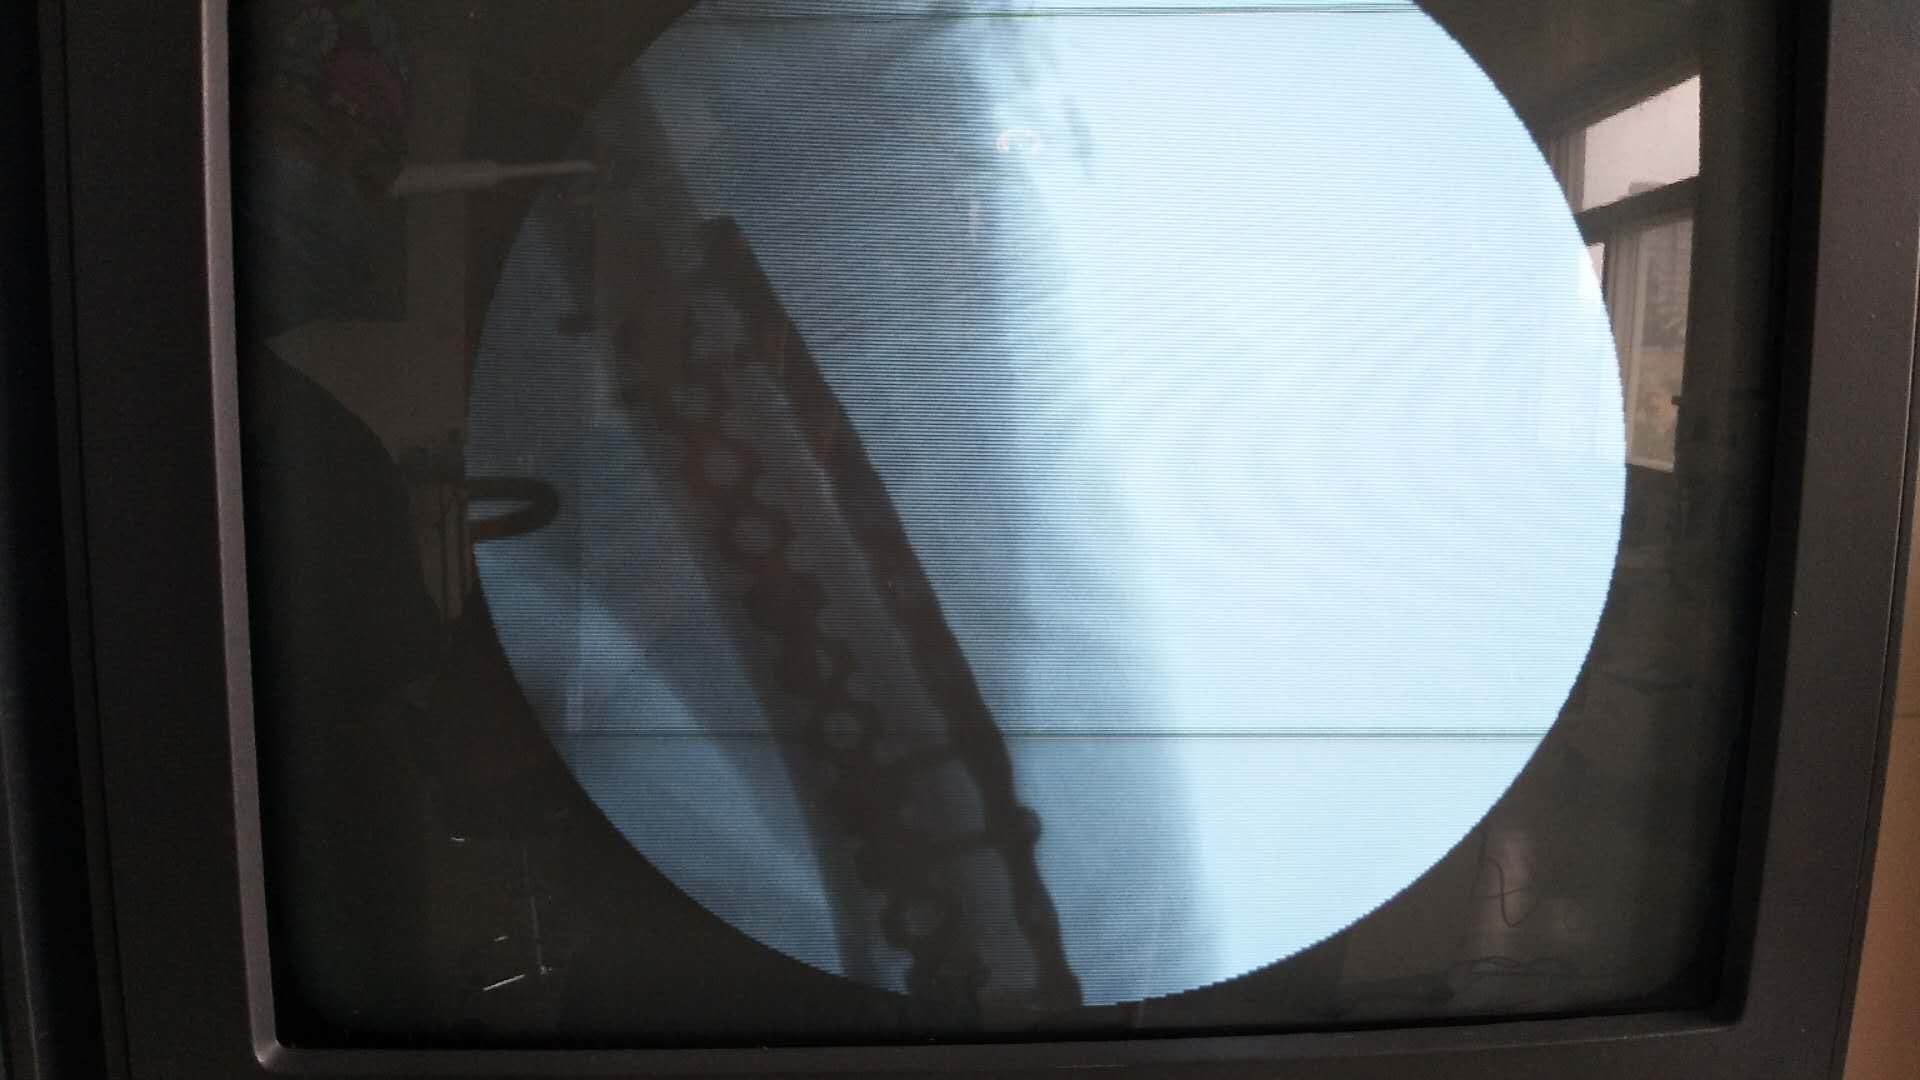

肱骨远端骨折(切复双钛板内固定)

摔伤后右肘部肿胀,畸形,活动受限2小时入院。既往身体健康,无特殊不良嗜好。从事健身教练工作数年。

生命体征平稳,心肺复未见异常。右上臂肿胀明显,畸形,局部皮色发红,皮温高,压痛及纵叩痛阳性,可及骨檫音及骨檫感,异常活动,末梢血运感觉正常。

诊断肱骨远端骨折在臂丛麻醉下行切复内固定术,术后抗炎,消肿等处理。